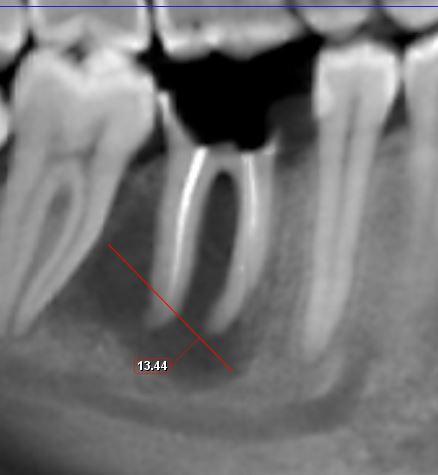

Доброго времени суток. Нужно профессиональное мнение. Два врача говорят только под удаление зуб. Третий - говорит можно попробовать ставить коронку. нужно еще мнение. Как вы считаете? Есть воспаление под зубом. Оно пройдет со временем и стоит подождать и поставить коронку или же тут гиблое дело и под удаление - имплант?